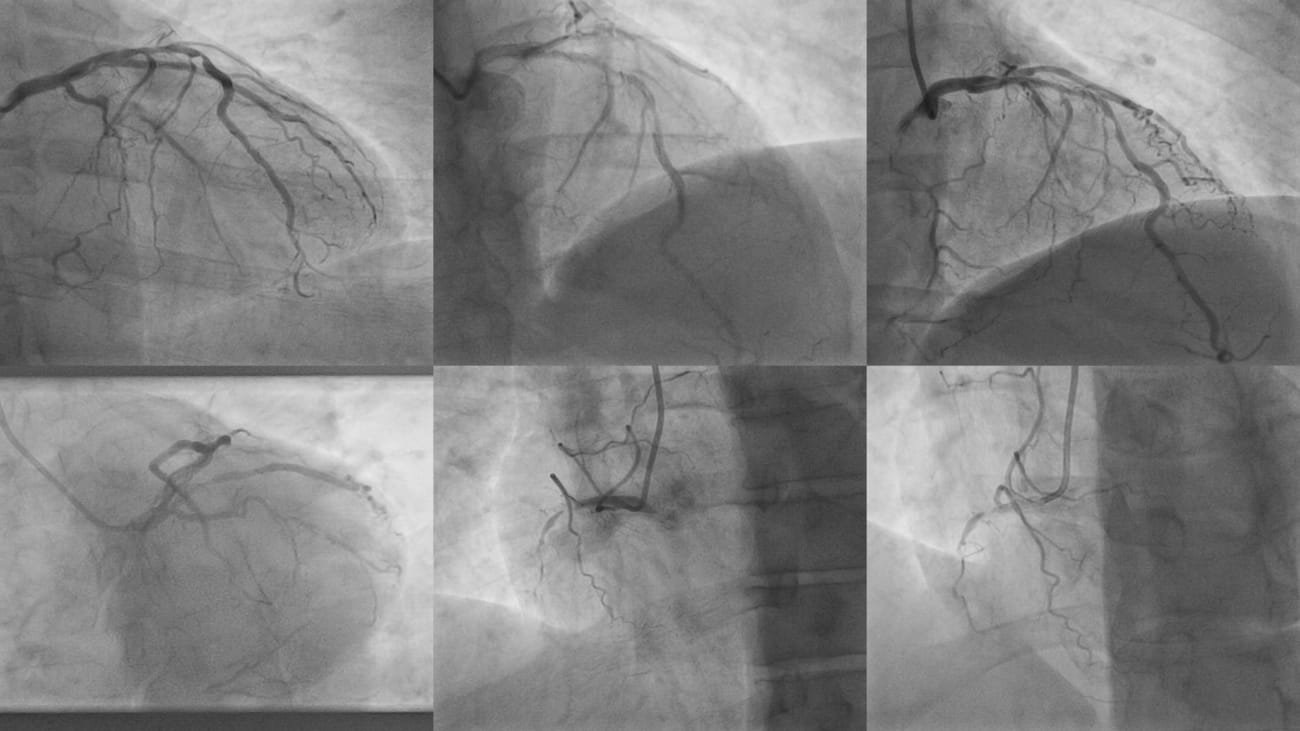

After the CCTA scan, Mr. Munoz immediately reported to his long-time cardiologist and his medical team outside of Baptist Health. He underwent a stent procedure, also known as coronary angioplasty, a minimally invasive medical intervention to open narrowed or blocked coronary arteries. The angioplasty opened up the coronary artery that was 95 to 97 percent occluded.

About a month later, he underwent “open heart bypass surgery,” also known as coronary artery bypass grafting (CABG), an open-chest surgical procedure that improves blood flow to the heart by creating new pathways around blocked coronary arteries. The surgery treated a second artery that was nearly completely blocked — and also detected by the MiHeart CCTA scan.